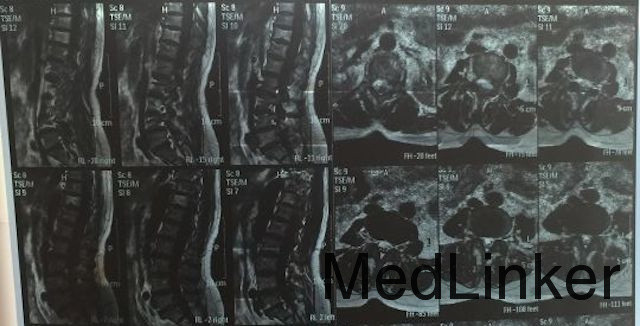

查体:T11及L2棘突压痛明显,脊旁压痛不明显,双下肢感觉、运动均无明显异常,会阴区感觉无异常。 辅助检查:脊椎MRI(如下图所示):T11及L2椎体T1信号较低,T2及T2抑脂相均为高信号,肿物边界清,椎间盘完整,考虑可能性大。

初步诊断:血管瘤可能性大 治疗:经皮椎体成形术+术中病理活检

随访:患者术后第二天疼痛缓解明显,术后病理回报为血管瘤。 讨论:患者为单纯性腰痛,无神经根症状,MRI示无明显神经受现象,椎间盘完整,肿物边界清晰,椎体及腰大肌周围未见脓肿形成,根据T1/T2及T2抑脂相,临床考虑椎体血管瘤可能性大,故可行椎体成形术。本患者主要需要鉴别的疾病为:腰椎盘突出、脊椎结核、脊椎肿瘤(一般转移瘤可能性大),确诊需病理。